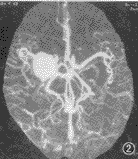

脑血管成像示:(1)55例CTA均可清楚显示1~4级脑血管结构、Willis环和大脑前、中、后动脉主干及其分支情况。(2)脑动静脉畸形12例,其中枕叶3例,颞叶5例,额叶3例,顶叶1例。可见异常增粗迂曲的血管,9例血管呈团状,5例可见增粗的引流血管,5例部分血管有钙化,均可清楚地观察到畸形血管的位置和范围(图1)。(3)动脉瘤2例,清楚地观察到瘤体大小、位置、形态,以及与血管的关系(图2,3)。(4)脑肿瘤19例,其中9例脑膜瘤可见肿瘤邻近血管被推移或包裹,4例可见肿瘤表面有异常血管(图4)。4例胶质瘤和4例转移瘤可见瘤体呈不均匀强化,或不强化,周围有不同程度水肿,肿瘤附近血管被推移(图5);位于第4脑室的室管膜瘤和位于中颅窝蝶骨翼旁的三叉神经瘤可见瘤体呈不同程度强化,室管膜瘤有血管推移。(5)大脑中动脉及分支栓塞3例,2例大脑中动脉主干变窄、变细,远侧方血管变细、变少(图6);1例大脑中动脉顶后分支变细,变窄,远侧方血管较少;(6)脑挫裂伤及脑脓肿可见局部血管有不同程度推移,脑积水以两侧大脑前、中动脉抬高较为明显。

图2 动脉瘤CTA,可见右中颅凹鞍旁有一球形病灶